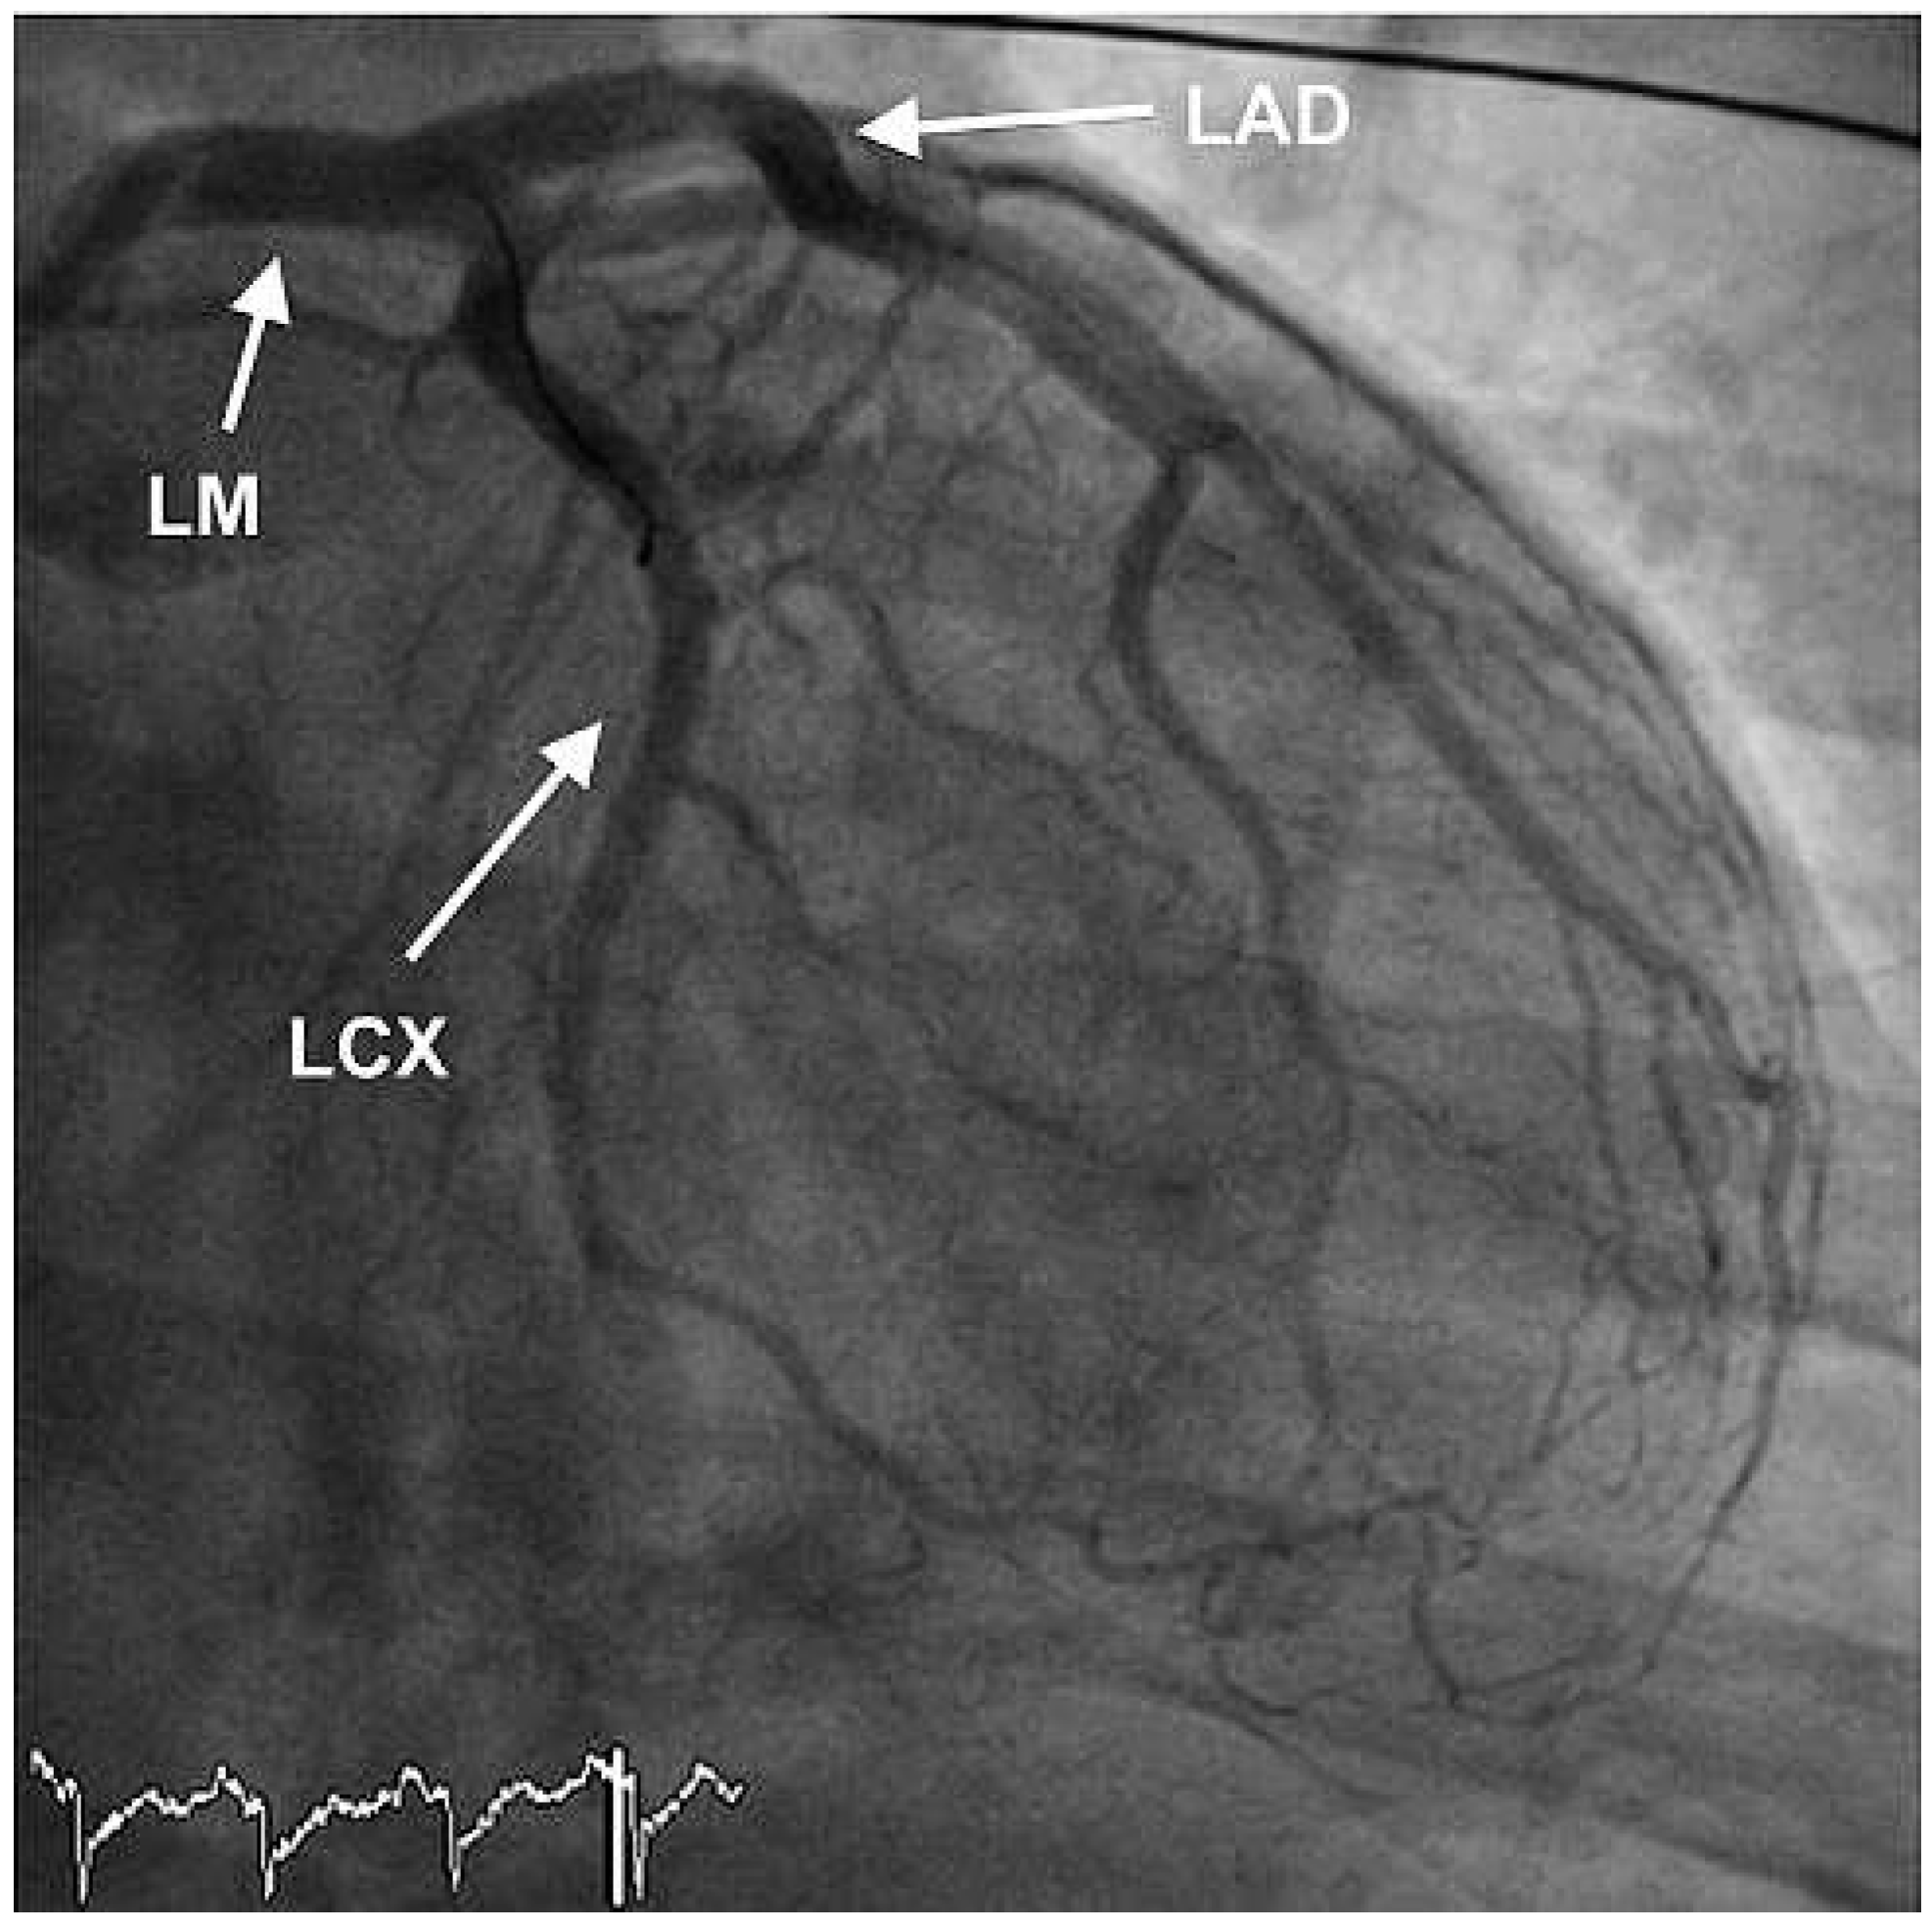

Furthermore, the right coronary artery showed a subtotal thromNo botic occlusion (Figure 3). Prior to the local treatment, a bolus of heparine 5000 IU and Abciximab were administered due to the heavy thrombus load. Thrombus aspiration was performed using an aspiration-catheter (Export AP, Medtronic) in all three coronary vessels. Due to persistent thrombotic material in the mid LAD, two low-pressure balloon inflations were done with a good end result (Figure 4 and Figure 5). There were no periprocedural complications. A treatment with life-long aspirin, one-year prasugrel, Betablocker and ACE-Inhibitor was initiated. The next day, a transesophageal echocardiography demonstrated improved LV-function (EF 50%) without evidence for an intracardiac thrombus or a patent foramen ovale (PFO).

Figure 5. LAO cranial view showing successful thrombus aspiration in the right coronary artery.